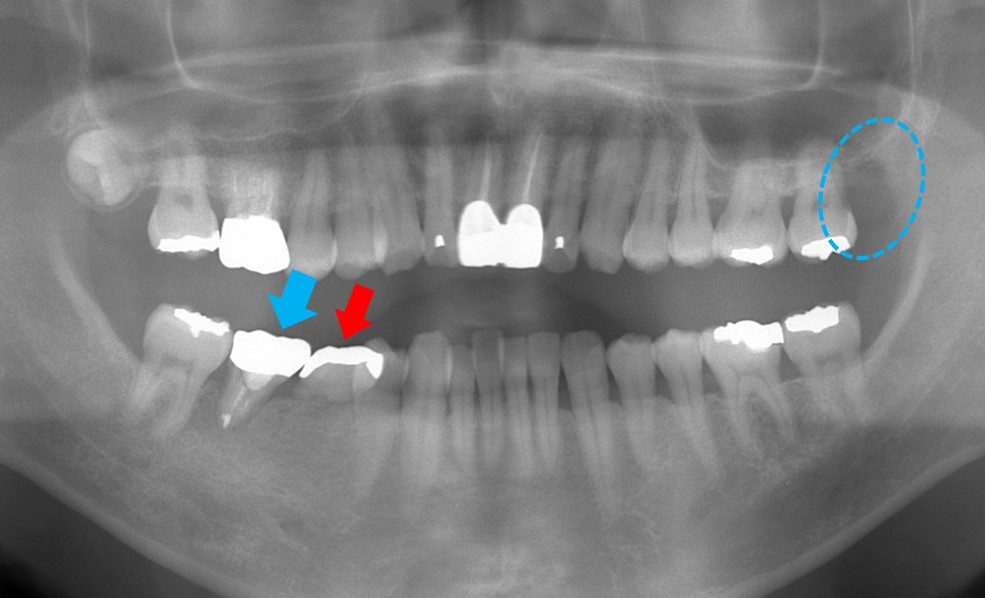

移植後、数カ月が経過した状態です。金属冠が装着され今のところ予後良好です。